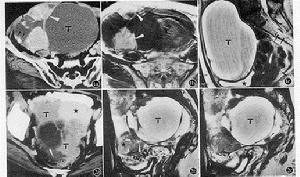

原發性卵巢絨癌原發性卵巢絨癌的特點:腫瘤多為單側性,右側較左側多見。腫瘤直徑8~30cm,為有包膜、實性、質軟而脆易碎的出血性腫物。多為棕紅色,有廣泛出血、壞死,常常在腫瘤邊緣找到少量存活的瘤組織。形態與子宮絨癌相同,如為混合型可出現其他生殖細胞腫瘤的形態。

2.絨癌典型的腫瘤體積較大,單側,實性質軟,出血、壞死明顯。形態同子宮絨癌如為混合性,則大體上可出現其他生殖細胞腫瘤的形態。